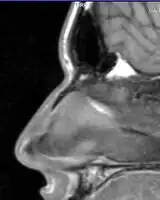

Nasal fractures are usually identified visually and through physical examination.[1] Medical imaging is generally not recommended.[1][2] A priority is to distinguish simple fractures limited to the nasal bones (Type 1) from fractures that also involve other facial bones and/or the nasal septum (Types 2 and 3). In simple Type 1 fractures X-Rays supply surprisingly little information beyond clinical examination. However, diagnosis may be confirmed with X-rays or CT scans, and these are required if other facial injuries are suspected.[2]

Nasal bone fracture